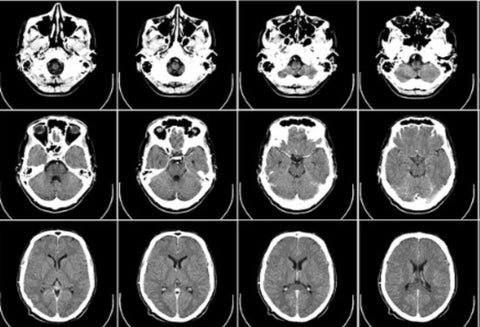

Esclerosis múltiple

Crédito: Imagen Referencial de uso libre- Pixabay